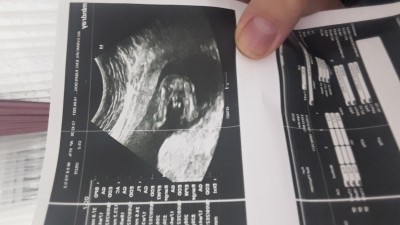

merhabalar 17 haftalik bacak arasinda kordonu girmis sizce cinsiyeti nedir erkeğe benziyor dedi ama ilerleyen zamanlarda daha belli olur dedi

Gebelik haftası 17 hafta 4 günlük